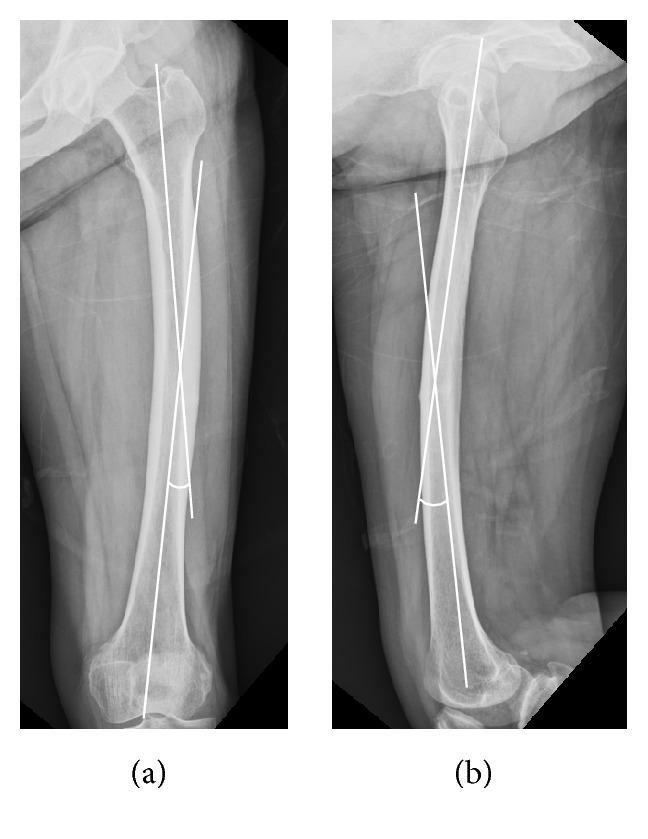

The purpose of our study was to investigate the radiographic characteristics of atypical femoral shaft fractures (AFSFs) in females with a particular focus on femoral bow and cortical thickness. We performed a fracture location-, age-, gender-, and ethnicity-matched case-control study. Forty-two AFSFs in 29 patients and 22 typical osteoporotic femoral shaft fractures in 22 patients were enrolled in AFSF group and control group, respectively. With comparing demographics between two groups, radiographically measured femoral bow and cortical thicknesses of AFSF group were compared with control group. All AFSF patients were females with a mean age of 74.4 years (range, 58-85 years). All had a history of bisphosphonate (BP) use with a mean duration of 7.3 years (range 1-17 years). Femoral bow of AFSF group was significantly higher than control group on both anteroposterior (AP) and lateral radiographs after age correction. Mean femoral bow on an AP radiograph was 12.39° ± 5.38° in AFSF group and 3.97 ± 3.62° in control group ( < 0.0001). Mean femoral bow on the lateral radiograph was 15.71° ± 5.62° in AFSF group and 10.72° ± 4.61° in control group (after age correction = 0.003). And cortical thicknesses of AFSF group demonstrated marked disparity between tensile and compressive side of bowed femurs in this study. An adjusted lateral cortical thickness was 10.5 ± 1.4 mm in AFSF group and 8.1 ± 1.3 mm in control group (after age correction < 0.0001) while medial cortical thickness of AFSF group was not statistically different from control group. Correlation analysis showed that the lateral femoral bow on the AP radiograph was solely related to lateral CTI ( = 0.378, = 0.002). AFSFs in female BP users were associated with an increased anterolateral femoral bow and a thicker lateral cortex of femurs.

我们的研究目的是探讨女性非典型股骨骨折(AFSFs)的影像学特征,特别关注股骨弯曲和皮质厚度。我们进行了一项骨折部位、年龄、性别和种族匹配的病例对照研究。42 例 AFSF 患者(29 例)和 22 例典型骨质疏松性股骨骨折患者(22 例)纳入 AFSF 组和对照组。比较两组患者的一般资料后,比较 AFSF 组和对照组的股骨弯曲和皮质厚度。所有 AFSF 患者均为女性,平均年龄 74.4 岁(58-85 岁)。所有患者均有双膦酸盐(BP)使用史,平均使用时间为 7.3 年(1-17 年)。校正年龄后,AFSF 组在前后位(AP)和侧位 X 线片上的股骨弯曲均明显高于对照组。AP 位 X 线片上 AFSF 组的平均股骨弯曲为 12.39°±5.38°,对照组为 3.97°±3.62°(<0.0001)。侧位 X 线片上 AFSF 组的平均股骨弯曲为 15.71°±5.62°,对照组为 10.72°±4.61°(校正年龄后 = 0.003)。本研究中,AFSF 组弯曲股骨的拉伸侧和压缩侧皮质厚度存在明显差异。AFSF 组的调整后外侧皮质厚度为 10.5±1.4mm,对照组为 8.1±1.3mm(校正年龄后 <0.0001),而 AFSF 组的内侧皮质厚度与对照组无统计学差异。相关性分析显示,AP 位 X 线片上的外侧股骨弯曲仅与外侧 CTI 相关( = 0.378, = 0.002)。女性 BP 使用者的 AFSF 与前外侧股骨弯曲增加和股骨外侧皮质增厚有关。